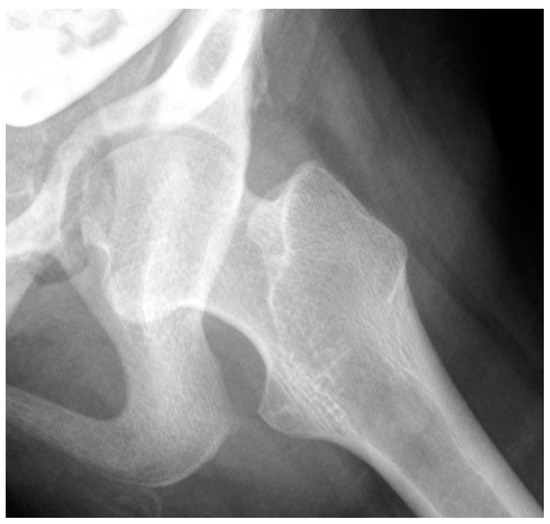

3.3.1. Impact of Abnormal Motor Function on Hip Development in Ambulatory Children

3.3.2. Pathology of Hip Development in Nonambulatory Children

4.1.1. Management of the Hip with High Pathologic Force Environment